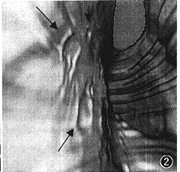

图3 同图2病例,FG示大小不等的黏膜糜烂伴出血病灶,大病灶(长箭头)周围黏膜苍白水肿明显,小病灶(短箭头)周围黏膜水肿轻微